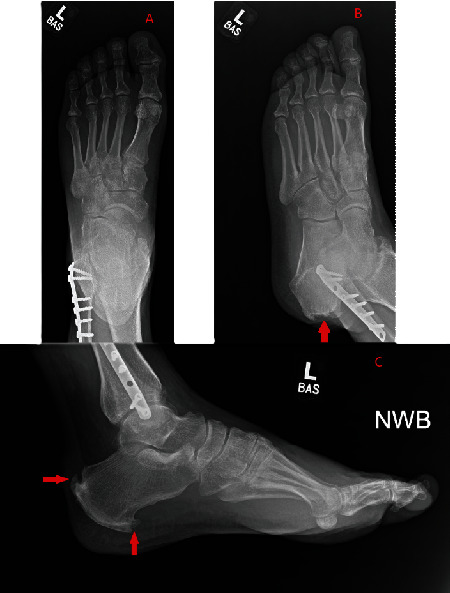

跟腱修复术后数年,之前的手术部位周围形成痛风性结石是一种极为罕见的病症,文献中仅记载过三例。在本病例中,我们报告了一名 53 岁男性的病例,他在两年半前进行过跟腱修复手术,并且没有痛风的临床病史,但在对跟腱进行必要的翻修手术时,我们发现他在初次手术修复时使用的不可吸收缝线周围出现了痛风性结石。这个病例和之前的三个病例都涉及到不可吸收缝合线的使用,这些缝合线有可能成为手术多年后痛风性跟腱炎形成的巢穴,即使是没有痛风临床病史的患者也可能出现痛风性跟腱炎。临床医生必须注意这种罕见的临床表现,因为潜在的后遗症包括感染过程和需要进行翻修手术。

The formation of gouty tophi surrounding the prior surgical site years after an Achilles tendon repair is an extremely rare presentation for which only three previous cases have been documented in the literature. In this case, we report the presentation of a 53-year-old male who had an Achilles tendon repair two and a half years prior and no clinical history of gout, yet during the necessary revision procedure of his Achilles tendon, he was found to have gouty tophi surrounding the nonabsorbable sutures used during his initial surgical repair. This case presentation and the three prior ones all involve the use of nonabsorbable sutures, and these sutures may potentially serve as a nidus for the formation of gouty tophi years after a surgical procedure, even in patients who do not have a clinical history of gout. It is important for clinicians to be aware of this rare clinical presentation as potential sequelae include infectious processes and the need for revision procedures.